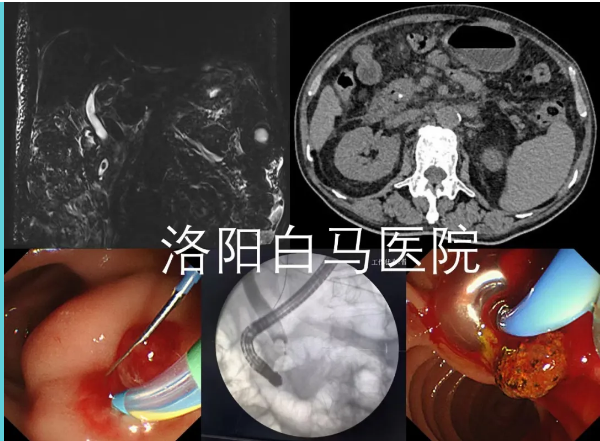

吕后宁主任首先为老人安排了上腹部CT检查。影像结果显示胆总管扩张,其末端可见高密度影,考虑结石可能。结合患者数年前曾有胆囊切除的病史,胆总管末端结石成为首要怀疑诊断。

为进一步明确结石的具体位置、大小,并排除其他可能引起梗阻性黄疸的病因(如胆管肿瘤、胆管狭窄等),随后为患者进行了MRCP检查。这项检查能更清晰地显示胆道系统的全貌。MRCP结果清晰证实了胆总管下端存在充盈缺损,即结石嵌顿,从而明确了胆总管末端结石”的诊断。这一严谨的步骤确保了诊断的准确性,为制定精准的治疗方案奠定了基础。

在充分的术前准备后,由陈宏伟主任与吕后宁主任共同为患者施行了ERCP取石术。术中,通过内镜精准定位,顺利将胆总管末端的结石取出,解除了胆道梗阻。